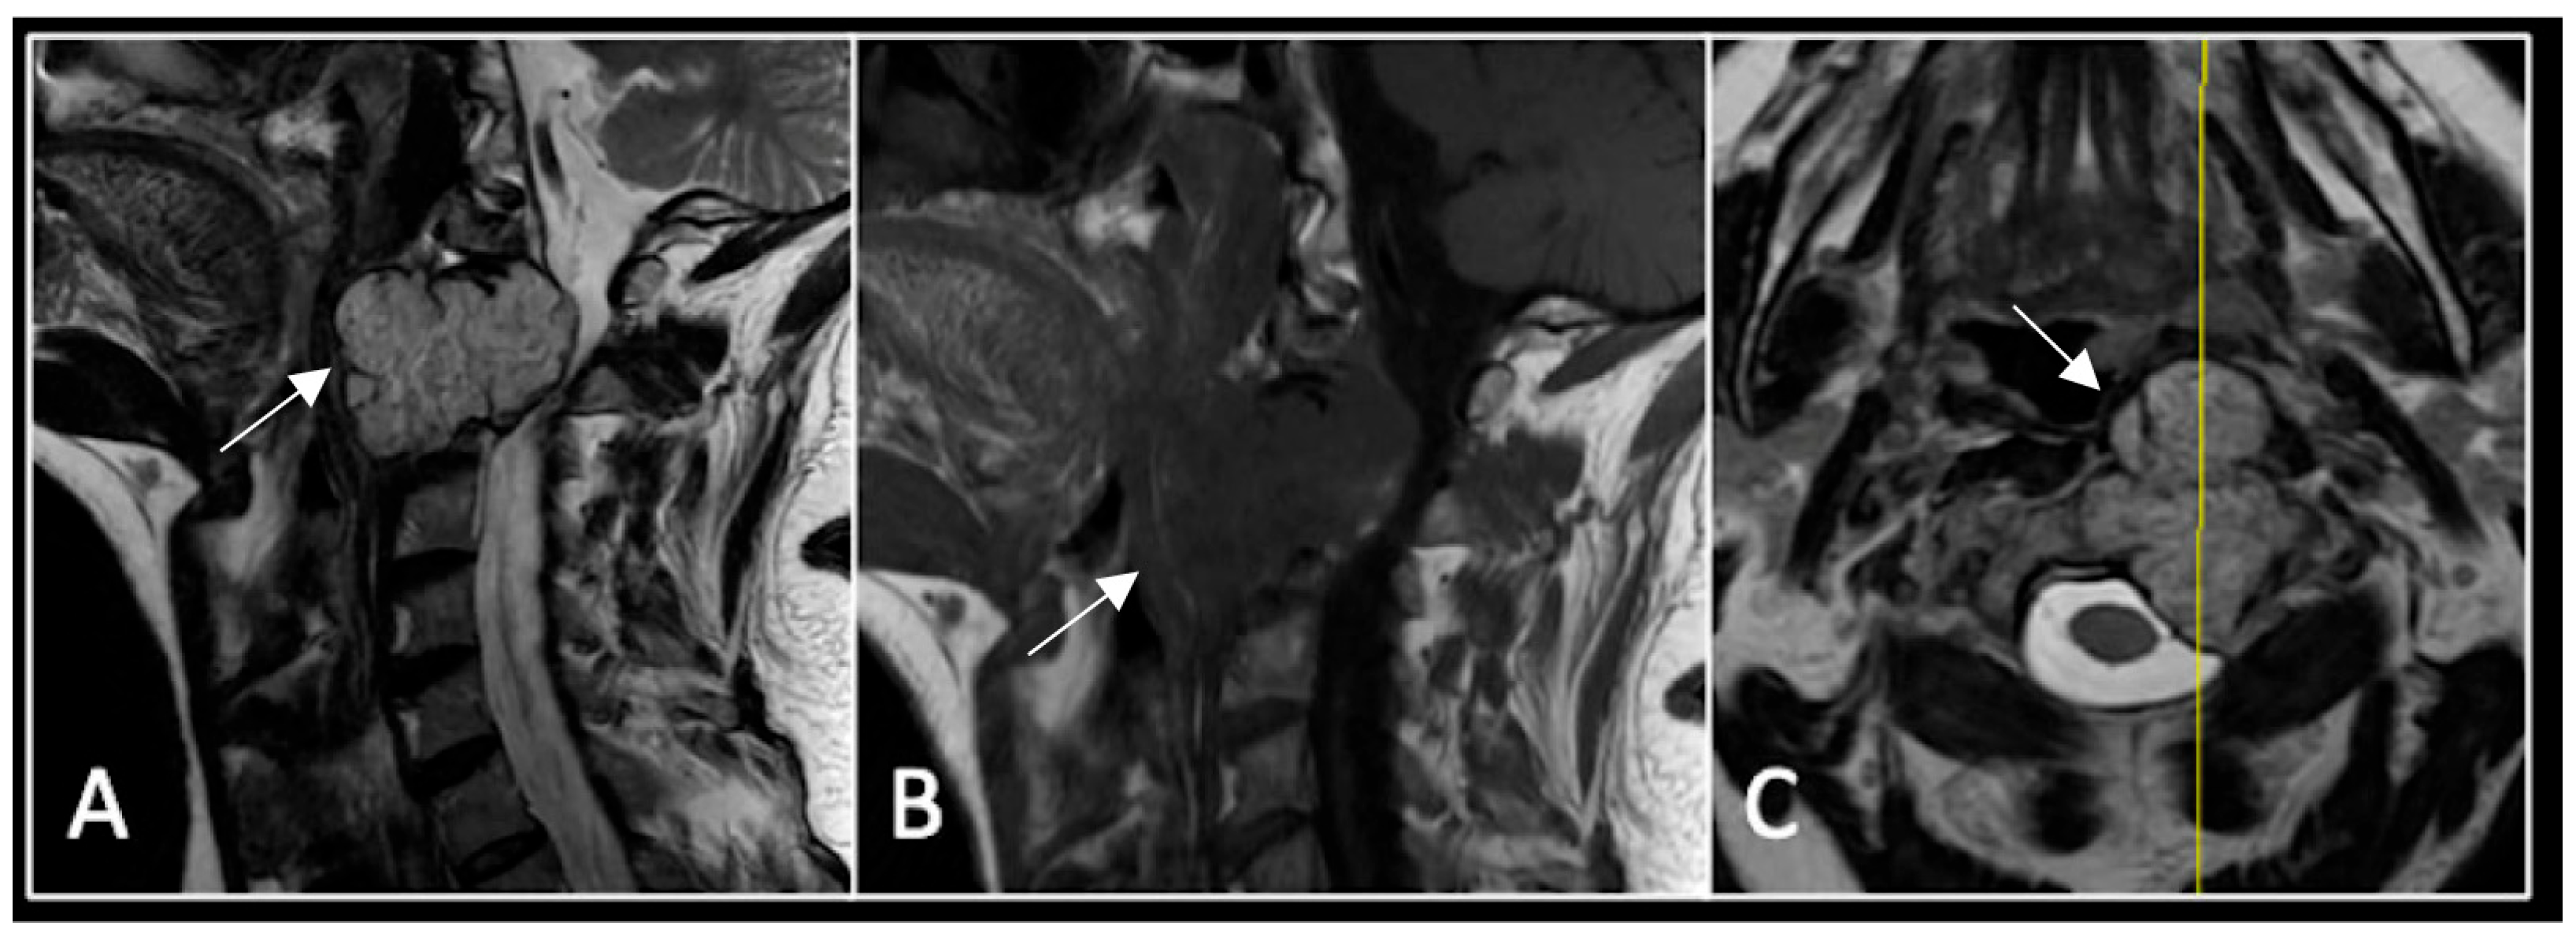

A 73-year-old male presented with an eight-month history of neck pain that was exacerbated on lying flat. He denied any symptoms of myelopathy and radiculopathy. He did not have any constitutional symptoms of malignancy. Past medical history included hypertension, renal cysts, and an ascending thoracic aneurysm. Examination was unremarkable. Diagnostic whole-spine MRI imaging demonstrated a large lobular mass localised to the cervical spine (Figure 2). Biopsy confirmed a conventional chordoma, and he underwent separation surgery followed by adjuvant proton beam therapy. Postoperative surveillance imaging at 12 months demonstrated stable disease (Figure 3).

Figure 3.

RI post-separation surgery showing reduction in tumour (arrow) dimensions and circumferential decompression. The posterior elements have been removed, and a posterior occipitocervical stablilsation has been performed. En-bloc resection would have necessitated sacrificing the left C2 nerve root and vertebral artery. The yellow line on the sagittal images indicates the level of the corresponding axial section. (A) T2W sagittal; (B) T1W sagittal; (C) T2-W axial.